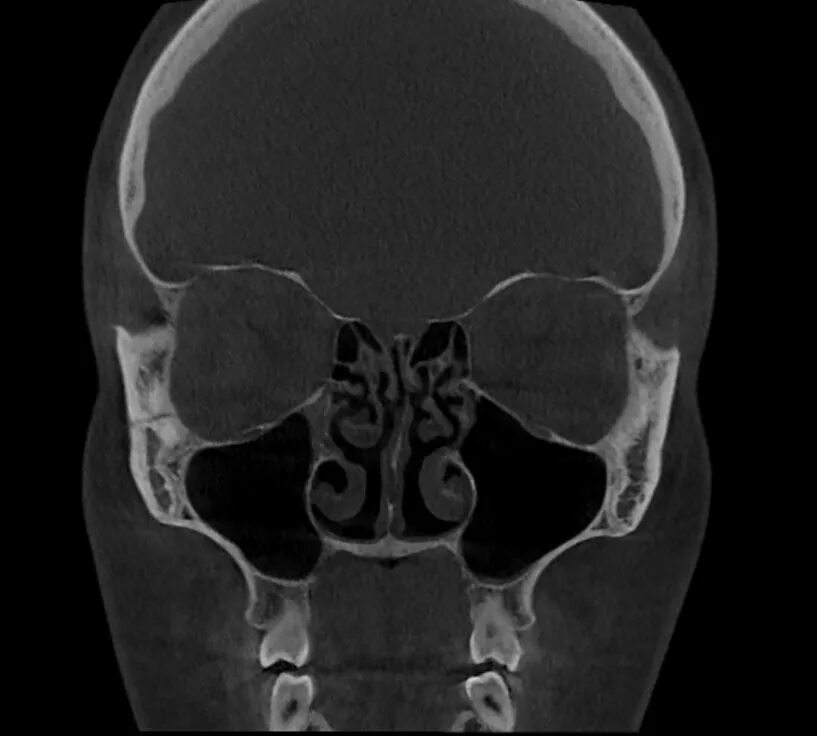

Сфеноидит симптомы